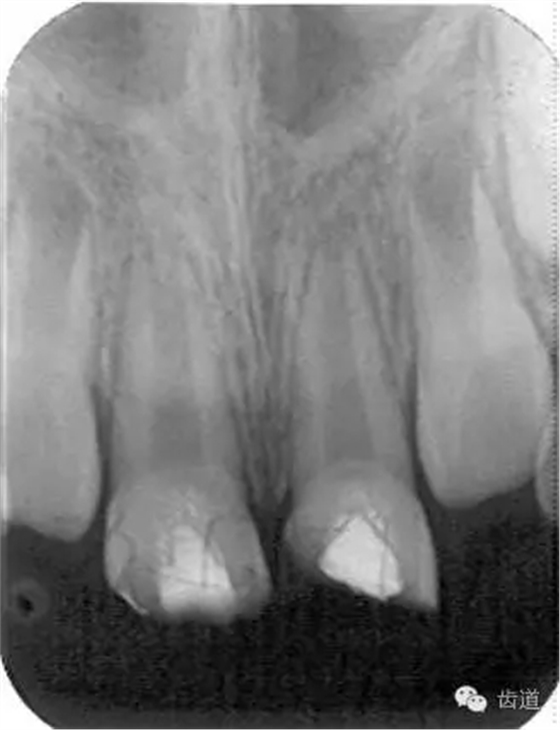

3個(gè)月左右在X線片上可觀察到修復(fù)性牙本質(zhì)層的出現(xiàn), 術(shù)后6個(gè)月左右,常可觀察到連續(xù)的有一定厚度的修復(fù)性牙本質(zhì)層; 修復(fù)性牙本質(zhì)層的出現(xiàn),是間接牙髓治療成功的重要指征。

牙本質(zhì)橋形成 formation of dental bridge